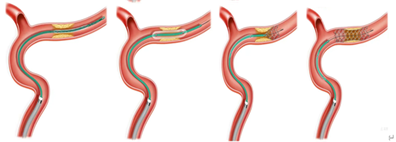

附:Fastunnel输送型球囊扩张导管"零交换"球囊扩张支架植入血管成形术技术要点

应用Fastunnel输送型球囊扩张导管"零交换"球囊扩张支架植入血管成形术减少术中导丝反复交换,球囊输送多个步骤,微导丝导引Fastunnel输送型球囊扩张导管一步到位接续球囊扩张,通过球囊扩张导管输送EP2支架回撤锚定狭窄位置后释放支架,减少导丝到达远端输送球囊、输送导管过程中并发症;

其次,Fastunnel输送型球囊扩张导管直径2.0、2.5mm,长度15mm,较其他颅内球囊略长,覆盖狭窄,扩张过程中发生夹层的方向降低。

第三、术中Fastunnel输送型球囊扩张导管头端、球囊远近段3个mak点清晰可见,能够精准锚定狭窄部位释放支架,达到支架精准植入。

Fastunnel输送型球囊扩张导管“零交换”手术方案示意图: